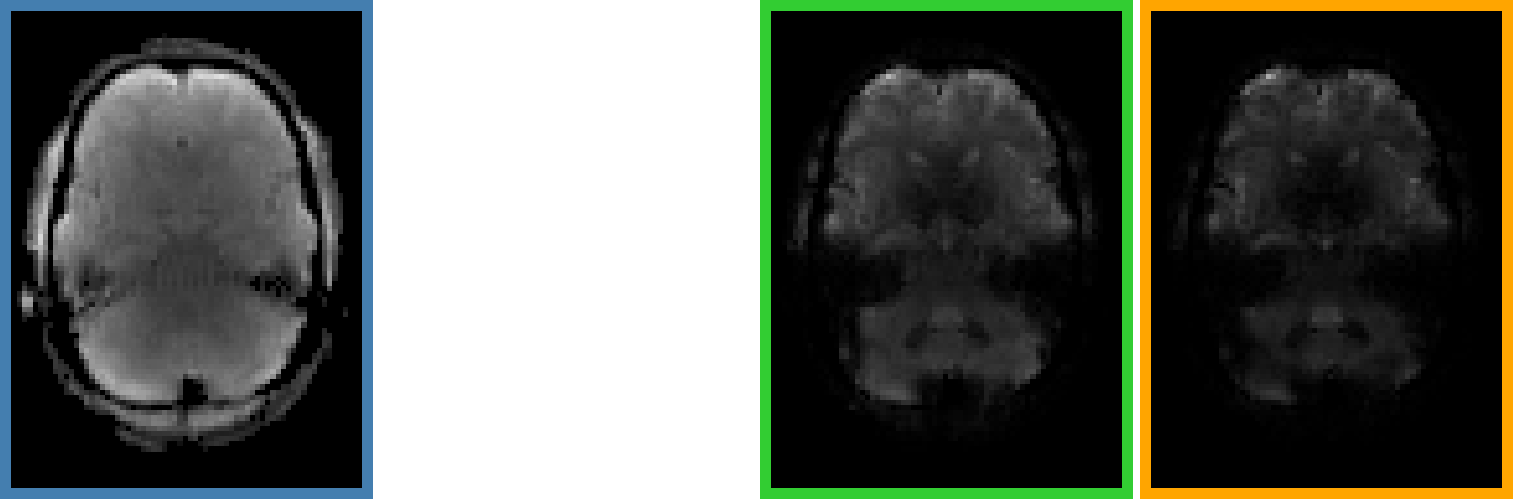

Multi Echo (ME-fMRI)

- Single Echo (SE): during fMRI acquisition we collect the signal once per TR at a certain TE to obtain one timeseries per voxel

-

Multi Echo (ME): we collect the signal multiple times at different TEs to obtain n timeseries per voxel

Multi Echo (ME-fMRI)

- Single Echo (SE): during fMRI acquisition we collect the signal once per TR at a certain TE to obtain one timeseries per voxel

-

Multi Echo (ME): we collect the signal multiple times at different TEs to obtain n timeseries per voxel

Optimal combination

For each voxel and TR, we can Optimally Combine the echo volumes with a weighted sum based on their contribution to \( T_2^{\star} \)

In this way, spatial CNR and tSNR are maximised and the signal can be recovered in areas of drop-out

Posse et al. 1999 (Magn Reson Med)

ME-ICA

Assuming monoexponential decay, we can express the

signal percentage change as:

\[ S_{SPC} \approx \Delta\rho - TE \cdot \Delta R_2^{\star} + n \quad where \enspace R_2^{\star} = \frac{1}{T_2^{\star}} \]

This let us differentiate BOLD-related (\(\Delta R_2^{\star}\)) from non-BOLD related (\(\Delta\rho\)) changes

Kundu et al. 2012 (NeuroImage)

If we apply ICA, we can fit the timeseries of the components to either sub-models and automatically classify them